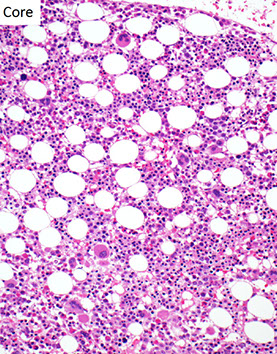

BM Findings

- markedly hypercellular (~100% cellularity)

- markedly elevated M:E ratio

Megakaryocytic hyperplasia and clustering.

-- "Dwarf mgkcs" - lots o small hypolobated megs

Marrow fibrosis (reticulin fibrosis) is variable

- marrow hypercellular w myeloid lineage inc and dwarf megakaryocytes (small + hypolobated)

-- BM fibrosis in 30% (get reticulin stain??), which is assoc w inc megakaryo # and poor prog